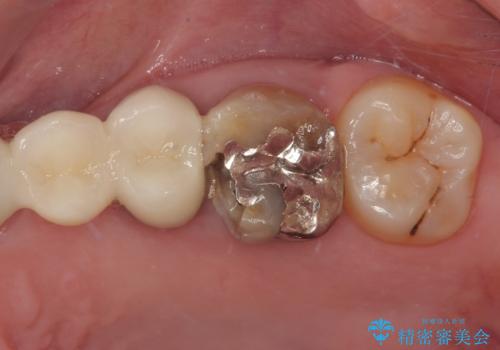

- 冷たいものがしみることがあるとのことで来院された患者様です。

銀歯の下にまでむし歯が及んでおり、レントゲン写真からも神経組織に迫っている状態が確認されました。

稀に冷たいものがしみる程度で、術前診査では神経を全て取る可能性は低いと予想されましたが、一部切除する可能性が高いことを伝えた上で治療を行うこととしました。

銀歯や欠損が大きいことから、虫歯治療後はオールセラミッククラウンによる補綴治療を行うこととしました。